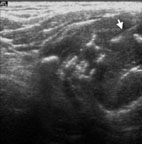

蔡先生因在左頸有腫塊而到耳鼻喉科門診就診(圖5),頭頸部的局部檢查除了左頸有界限糢糊不清的腫塊外其它包括鼻咽部(圖6)並沒有明顯異常,以頭頸部超音波檢查發現淋巴結預測值高於7分(圖7),超音波導引下細針穿刺細胞學檢查懷疑是轉移性鼻咽癌後,接受內視鏡鼻咽部切片證實為鼻咽癌。由於蔡先生超音波導引下細針穿刺細胞學檢查,避免了過去常見的頸部腫塊的切片手術。蔡先生接受放射腺治療後,腫塊即消失,因此可見頸部腫塊的切片手術對於鼻咽癌的診斷治療是不必要的。

圖7. 頭頸部軟組織超音波檢查,惡性淋巴結預測值高於7分,超音波導引下細針穿刺懷疑是轉移性鼻咽癌,後由鼻咽部切片證實為鼻咽癌